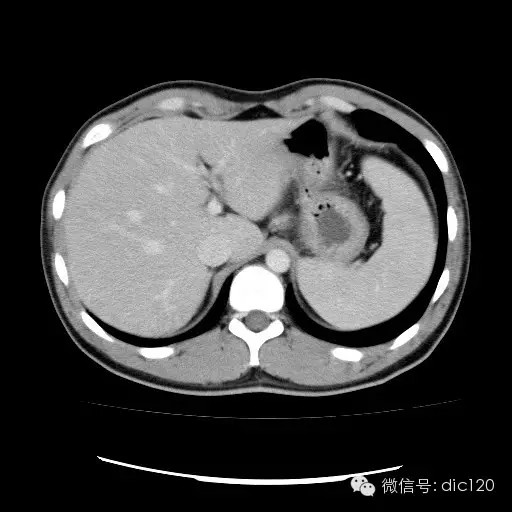

| 影像表现及分析: | 影像表现:动脉期扫描肝右叶紧贴边缘见一过性楔形高密度强化区,边界清,边缘平直,临近血管走形自然,门静脉期期恢复正常肝实质密度,延迟保持与肝实质密度一致。 |

| 疾病总结: | 正常肝脏的双重血供并非2个独立系统,两者之间有许多交通吻合,包括①肝窦间通路.②脉管间途径.③血管丛途径,即胆管周围血管丛途径.当肝脏发生血供障碍时,通过神经一体液因素的调节这些交通吻合支开放,双重供血发生血流量的变化甚至血流方向的改变.肝脏的这种”一过性”灌注异常在SCT表现为肝动脉期一过性肝实质强化(THPE).一过性肝实质强化差异是SCT增强扫描于肝动脉期表现的肝脏一过性灌注异常,大多数情况下它反映了局部肝脏双重血供的重新分布,即局部肝实质门静脉或肝静脉血流量减少,肝动脉血流量增多或为肝动脉门静脉分流或局部肝脏的变异或迷走血供所致。典型CT表现为肝动脉期一过性楔形或三角形高密度强化区,边缘平直,常位于肝脏边缘部位,其中血管走行正常,门静脉期恢复为正常肝实质密度。放射学医师应加强对一过性肝实质强化CT表现的认识。 |